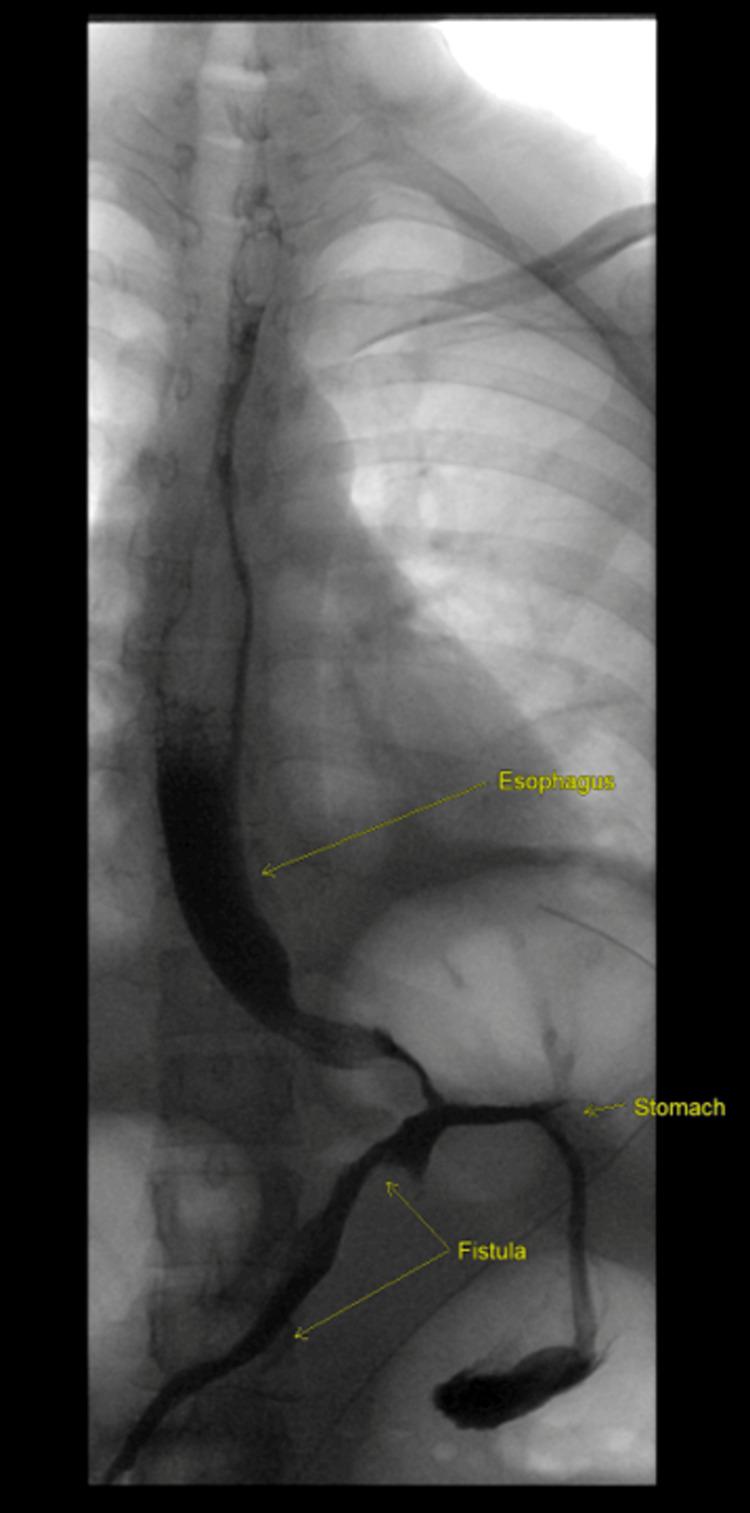

Obesity is an important public health concern worldwide. In Saudi Arabia, the overall prevalence of obesity has increased in both men and women in recent decades. The laparoscopic approach to bariatric surgery was first reported in the 1990s, with laparoscopic adjustable gastric banding (LAGB) developed soon after. The performance of bariatric procedures has increased rapidly in recent years, with safety and efficacy data available for the surgical treatment of obesity and related metabolic disorders. Herein, we report a challenging condition of a female patient who underwent LAGB insertion in 2013. The patient presented with a complaint of a foreign body passing through her rectum during defecation that was manually pushed back by the patient. Radiological imaging and upper/lower endoscopy confirmed the diagnosis of complete gastric band erosion into the stomach, and the reservoir with the remaining tube was observed inside the colon near the splenic flexure. This case was complicated by complete band erosion and gastrointestinal (GI) fistula formation following the delivery of her second child in January 2022. Colonic band erosion is a rare complication of LAGB. Most patients with gastric band erosion are asymptomatic or exhibit nonspecific symptoms. The definitive management of gastric band erosion involves band removal. Several approaches are commonly used in clinical practice. In our case, the band was removed using a combined laparoscopic and endoscopic retrieval approach, which is the first such report in the literature.

肥胖是全球重要的公共卫生问题。在沙特阿拉伯,近几十年来,男性和女性的肥胖总体患病率均有所上升。腹腔镜减肥手术方法于20世纪90年代首次报道,随后不久便开发出了腹腔镜可调节胃束带术(LAGB)。近年来,减肥手术的实施迅速增加,有关于肥胖及相关代谢紊乱手术治疗的安全性和有效性数据。在此,我们报告一例具有挑战性的病例,一名女性患者于2013年接受了LAGB植入术。患者主诉排便时有异物从直肠排出,患者自行将其推回。放射影像学检查及上/下消化道内镜检查确诊为胃束带完全侵蚀入胃,在脾曲附近的结肠内观察到带有剩余导管的贮液器。该病例在2022年1月患者分娩第二个孩子后并发胃束带完全侵蚀和胃肠道(GI)瘘形成。结肠束带侵蚀是LAGB的一种罕见并发症。大多数胃束带侵蚀患者无症状或表现出非特异性症状。胃束带侵蚀的最终治疗方法是取出束带。临床实践中常用几种方法。在我们的病例中,采用腹腔镜和内镜联合取出束带的方法,这是文献中首次此类报道。